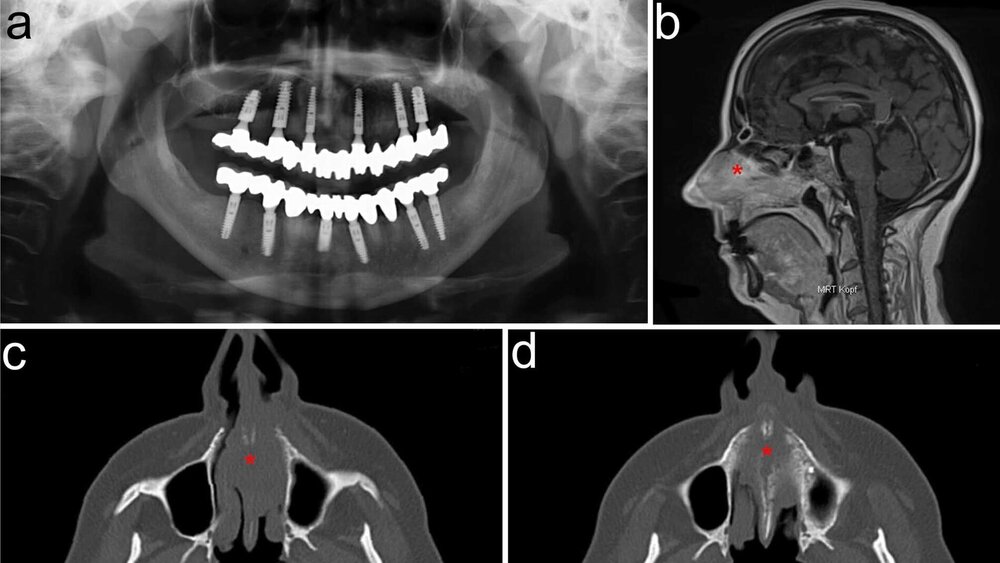

Klinisch zeigte sich bei der anterioren Rhinoskopie eine tumoröse solide Masse, die die vordere Nasenhöhle ausfüllte. Die Computertomografie (CT) und Magnetresonanztomografie (MRT) ergaben den Verdacht auf einen Tumor mit Infiltration des Oberkiefers, der Nasenhaupthöhle, des Gaumens und des angrenzender Nasen- Rachenraums (Abbildung 1).

Die histopathologische Aufarbeitung einer Probeexzision erbrachte die Diagnose eines adenoidzystischen Karzinoms (ACC). Das Tumorstaging ergab zwar einen fortgeschrittenen Lokalbefund, jedoch keine Schädelbasisbeteiligung.